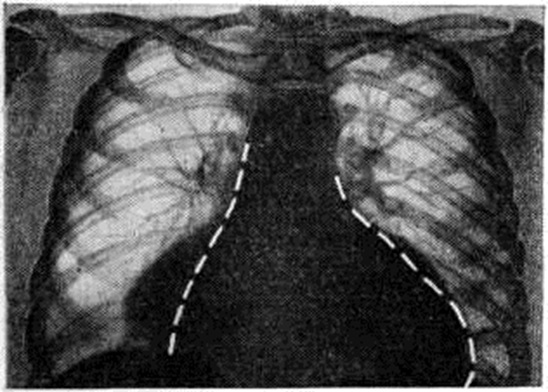

Вторичный Гипотиреоз отличается от первичного меньшей выраженностью симптомов, наличием патологический процесса в гипоталамогипофизарной системе, значительным снижением деятельности коры надпочечников и половых желез в связи с недостаточной секрецией адренокортикотропного и гонадотропных гормонов гипофиза. Рентгенологическое исследование выявляет изменения в сердце и желудочно-кишечного тракте. Рентгенологическое картина сердца характеризуется значительным увеличением его размеров, медленными и вялыми сокращениями. Нередко обнаруживают наличие жидкости в перикарде, исчезающей или значительно уменьшающейся в процессе заместительной гормональной терапии (рисунок 2). В желудочно-кишечного тракте — понижение моторики кишечника и отёк слизистой оболочки. Костная система у взрослых при Гипотиреоз не нарушается. Дифференциально-диагностическое значение имеет проба с тиреотропным гормоном (смотри полный свод знаний). При вторичном Гипотиреоз после введения 5—10 ЕД тиреотропного гормона нормализуется поглощение радиоактивного йода щитовидной железой и содержание в крови йода, связанного с белком; при первичном Гипотиреоз эти показатели остаются сниженными. Внешнее сходство с больными Гипотиреоз могут иметь больные с хронический нефритом, но наличие изменений в моче позволяет дифференцировать Гипотиреоз от поражения почек. ЛечениеПитание больных Гипотиреоз должно быть полноценным; при ожирении необходимо ограничение калорийности пищи. Назначают витамины С, группы В и А; при развитии гипохромной анемии — препараты железа, при гиперхромной — витамин В12. Медикаментозное лечение сводится к назначению соответствующих доз тиреоидных препаратов, постепенно устраняющих симптомы Гипотиреоз. Применяют высушенный препарат щитовидной железы — тиреоидин, тироксин и трийодтиронин. Действие тиреоидина определяется в основном тироксином. Суточную дозу для каждого больного устанавливают путём постепенного повышения количеств вводимых гормонов. Целесообразно одновременное введение тиреоидина или тироксина и трийодтиронина, что обеспечивает необходимую для организма активность щитовидной железы. Тироксин действует медленно, трийодтиронин быстро и более энергично, поэтому целесообразно подбирать суточную дозу, изменяя количество трийодтиронина. Больным молодого и среднего возраста без изменений венечных сосудов сердца назначают тиреоидин по 0,1—0,2 грамм в сутки и с добавлением трийодтиронина по 5— 10 микрограмм каждые 3—5 дней до нормализации частоты пульса и уменьшения других симптомов. При передозировке возможны явления тиреотоксикоза (смотри полный свод знаний), которые исчезают после отмены трийодтиронина или временного уменьшения его дозы. Больным первичным Гипотиреоз и ишемической болезнью сердца назначать тиреоидные препараты следует с осторожностью, так как усиление деятельности миокарда может вызвать острую коронарную недостаточность. Начальные дозы тиреоидина 0,005— 0,01 грамм 2 раза в сутки. Если нет ухудшения показателей ЭКГ и отсутствуют признаки стенокардии, через 5—10 дней дозу тиреоидина увеличивают на 0,01 грамм. При применении трийодтиронина начальная суточная доза 5—10 микрограмм, тактика наблюдения такая же. При развитии гипотиреоидной комы назначают трийодтиронин по 100 микрограмм 2 раза в сутки, больным с коронарной недостаточностью по 10 микрограмм 2—3 раза в сутки. После выведения из комы суточную дозу постепенно уменьшают. При вторичном Гипотиреоз перед назначением тиреоидных препаратов для устранения явлений гипокортицизма назначают глюкокортикоиды. Лечение психических нарушений состоит прежде всего в лечении основного эндокринного заболевания (заместительная гормональная терапия); применяют также симптоматические психофармакологические средства (стимуляторы, антидепрессанты и тому подобное). ПрогнозПри первичном Гипотиреоз своевременное и правильное лечение устраняет симптомы Гипотиреоз, восстанавливает трудоспособность, однако выздоровление не наступает и при отмене тиреоидных препаратов наблюдается рецидив. При вторичном Гипотиреоз прогноз зависит от характера поражения гипоталамогипофизарной области и степени выпадения функций гипофиза. Профилактика приобретённого Гипотиреоз связана с совершенствованием техники хирургического вмешательства на щитовидной железе, с правильным подбором дозы радиоактивного йода при лечении тиреотоксикоза, с осторожным лечением препаратами обычного йода, с целенаправленным и ранним лечением острого и подострого тиреоидита. Гипотиреоз у детей так же, как и у взрослых, разделяют на первичный и вторичный. Первичный Гипотиреоз может быть врождённым — спонтанный кретинизм (смотри полный свод знаний) и приобретённым (ювенильный гипотиреоз). Гипотиреоз является одним из самых распространённых эндокринных заболеваний у детей. Этиология приобретённого Гипотиреоз не отличается от этиологии первичного Гипотиреоз у взрослых. Врождённый Гипотиреоз развивается при гипоплазии тиреоидной ткани, её эмбриональных дистопиях, а также при нарушении биосинтеза тиреоидных гормонов в виде дефекта поглощения йодида щитовидной железой, отсутствия органического связывания йодида, нарушения дегалоидирования йодтирозинов, дефекта конденсации йодированных тирозинов в йодтиронины, образования патологический йодпротеина. Патогенез связан с недостатком в организме ребёнка йодсодержащих гормонов. Патологоанатомические изменения. Для врождённого Гипотиреоз характерно недоразвитие половых желёз, резко выраженные изменения костной системы: задержка роста, процессов окостенения и дифференцирования скелета; деформации черепа, нарушение развития хрящевой ткани эпифизов трубчатых костей с последующими изменениями в оссификации — многочисленными неправильными фокусами, рассеянными по всей зоне изменённого хряща (так называемый эпифизарный дисгенез). Эти же изменения наблюдают у детей, заболевших в раннем возрасте. Гипотиреоз в раннем детском возрасте приводит также к задержке развития головного мозга и к дистрофическим явлениям в нервных клетках коры, продолговатого мозга и мозжечка (хроматолиз, вакуолизация, эксцентрическое положение ядер). Клиническая картинаЧасть детей с врождённым Гипотиреоз при рождении весит больше 4000 грамм, физиологический желтуха у них носит затяжной характер, позднее обычного отпадает пупочный канатик, возможно образование грыжи. Дети плохо берут грудь. К 3—6 месяцев обращает на себя внимание вялость и безразличие ребёнка, он не узнает мать, не интересуется игрушками. Кожа бледная, сухая, холодная на ощупь, общая одутловатость. Выявляются задержка в росте и отставание в физических и умственном развитии. Дети в обычные сроки не держат голову (рисунок 3), не садятся; ходить начинают только после 2—3 лет. Голова по сравнению с туловищем большая, теменной родничок остаётся открытым у детей старше 2 лет. Прорезывание зубов запаздывает, они быстро разрушаются. Волосы редкие, сухие, ломкие. Голос низкий, грубый. Живот увеличен, метеоризм, характерны запоры. Рост резко замедлен, точки окостенения появляются поздно. Часто отмечается брадикардия, артериальная гипотензия, глухость тонов сердца; изменения ЭКГ такие же, как у взрослых, но менее выраженные. Наблюдается задержка умственного развития, медлительность, вялость, безразличие, иногда агрессивность, возможны нарушения психики. Степень выраженности нарушений, и в частности микседематозного отёка, варьирует. При приобретённом Гипотиреоз, развившемся после 6—10 лет, клинической, картина такая же, как у взрослых, но обычно с менее выраженными симптомами.